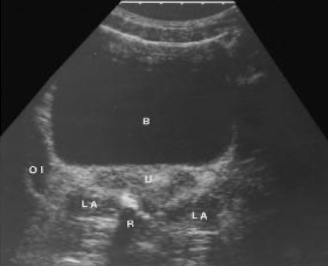

SONO: vagina, cervix, uterus

TA pelvic anatomy in TRANS

starting TRV is easiest way to find ovaries